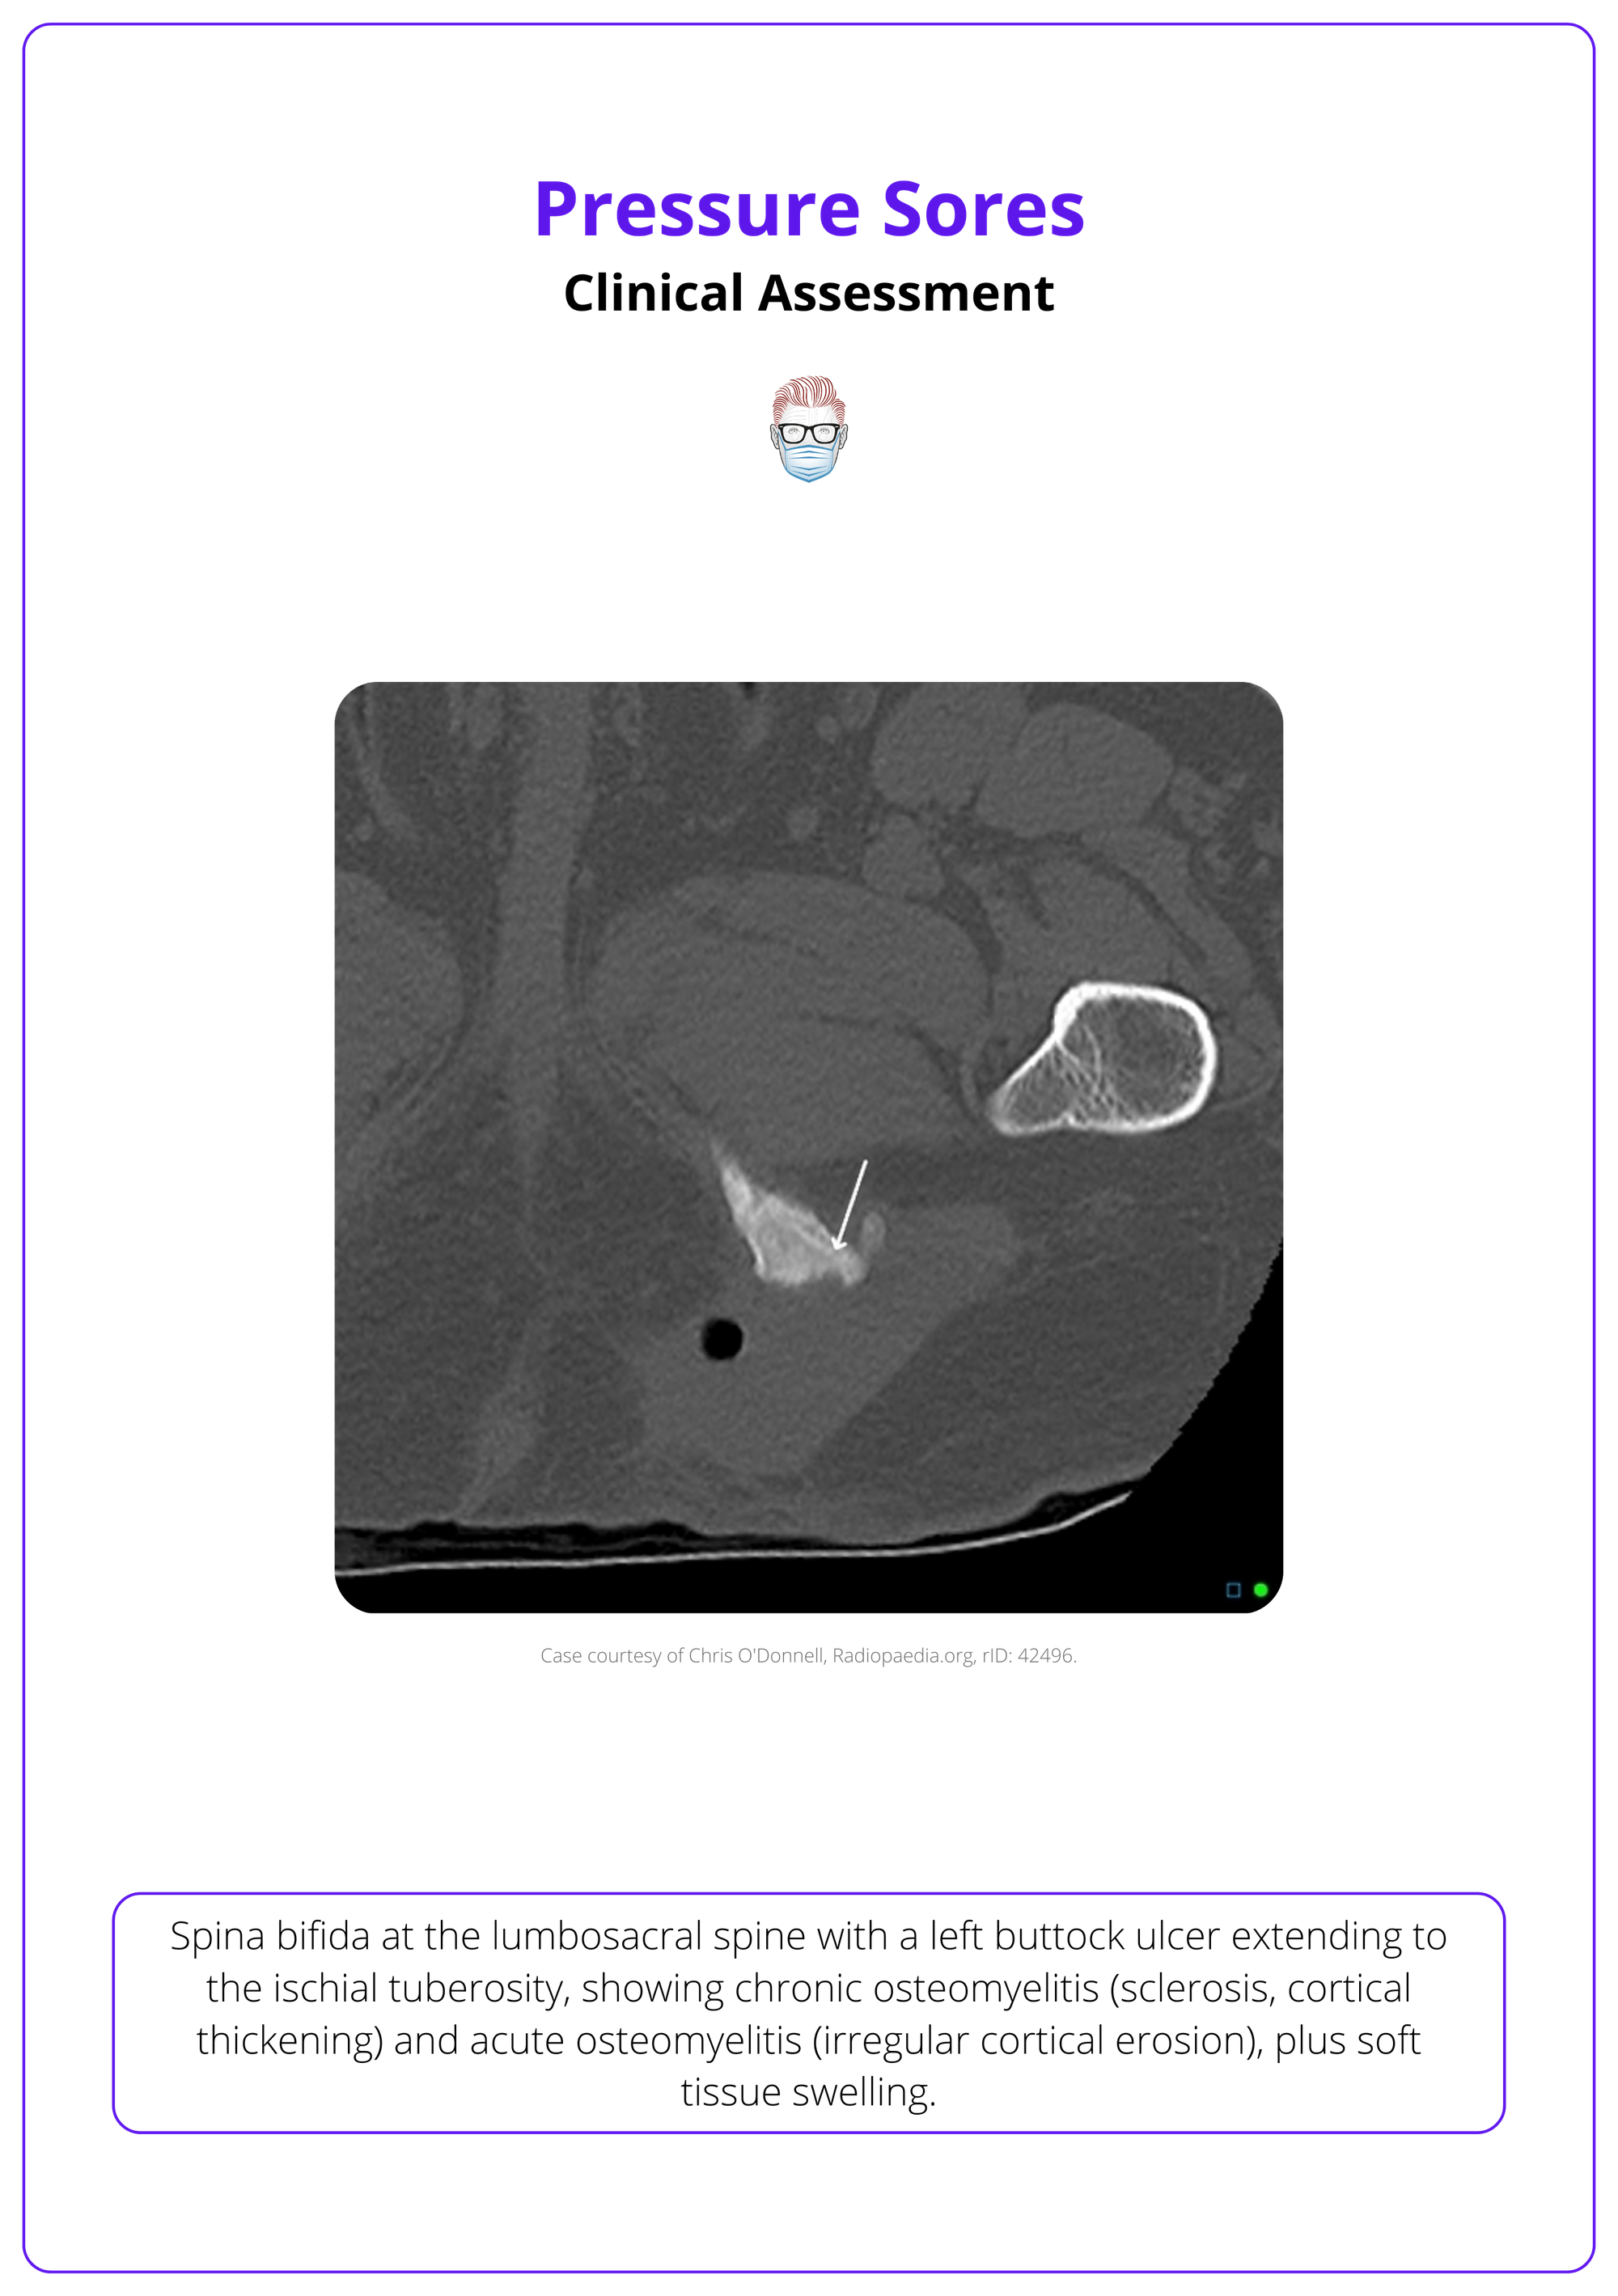

The image below illustrates the clinical assessment of a left buttock ulcer extending to the ischial tuberosity.

Evaluating pressure sores involves taking a comprehensive history, grading the ulcer, and using lab tests and imaging to identify complications such as osteomyelitis.

- MRI or CT: Essential for identifying osteomyelitis, abscesses, or deep tissue involvement.